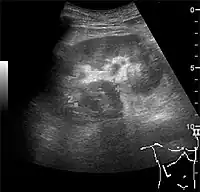

Complex cysts can have membranes dividing the fluid-filled center with internal echoes, calcifications or irregular thickened walls. The complex cyst can be further evaluated with Doppler US, and for Bosniak classification and follow-up of complex cysts, either contrast-enhanced ultrasound (CEUS) or contrast CT is used (Figure 6). The Bosniak classification is divided into four groups going from I, corresponding to a simple cyst, to IV, corresponding to a cyst with solid parts and an 85–100% risk of malignancy.[1] In polycystic kidney disease, multiple cysts of varying size in close contact with each other are seen filling virtually the entire renal region. In advanced stages of this disease, the kidneys are enlarged with a lack of corticomedullary differentiation (Figure 7).[1]

- Figure 7. Advanced polycystic kidney disease with multiple cysts.[1]